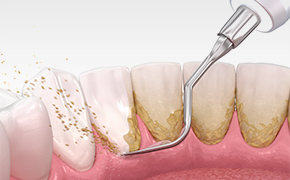

スケーリング

歯石の蓄積は歯周病菌などの細菌を増殖させて、歯科疾患の原因となります。そのため、スケーラーという専用の器具を使用して、歯に付着した歯石を取り除きます。基本的な歯周病治療の一種です。

SRP

スケーリング、ルートプレーニングの略からSRPと呼ばれており、歯周病治療の一環として行われます。歯の表面や根元に付着した歯石を徹底的に取り除くとともに、歯垢やバイオフィルムの再付着を防ぐ効果も期待できます。